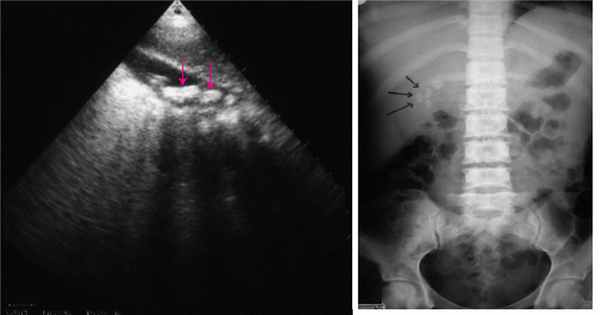

«Золотым стандартом» диагностики дивертикулярной болезни является ирригоскопия. Этот метод позволяет определить количество дивертикулов, их точное местоположение, размеры и форму. Суть процедуры заключается в введении рентгенконтрастного препарата в толстую кишку, после этого выполняется серия рентгенологических снимков, позволяющих оценить состояние толстой кишки. На представленных фотографиях стрелками указаны устья дивертикулов толстой кишки. Синими стрелками мы отметили множественные дивертикулы ободочной кишки. Именно так они выглядят при компьютерной томографии.

Рисунок 4. Ирригоскопия. Дивертикулез толстой кишки

На рентгенологических снимках, выполненных при ирригоскопическом исследовании, отчетливо видны множественные дивертикулы ободочной кишки. Они выглядят как мешочки, заполненные рентгеноконтрастным препаратом.

Не менее важными методами являются ультразвуковая диагностика и компьютерная томография. Благодаря своей малоинвазивности, простоте выполнения, ультразвуковая диагностика очень актуальна на этапе первичного обследования. Она позволяет увидеть наличие дивертикулов, выявить косвенные признаки их воспаления, такие как инфильтрат, абсцесс или предположить генерализованную форму – перитонит.